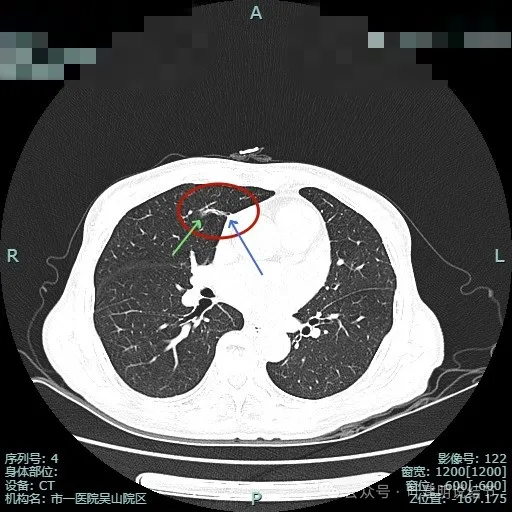

病灶较小了些,但给人感觉收缩力仍强,细支气管有扩张与截断。

边缘区小片状,但仍有收缩力与边界较清。

条索区域了,仍有毛刺征,纵隔侧有轻微胸膜牵拉。

边缘区磨玻璃条状,也有毛刺样征。